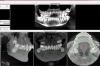

Большой Зеленый Опубликовано 13 марта, 2013 Поделиться Опубликовано 13 марта, 2013 Чтобы получить полезную информацию нужны снимки .Ортопантомограмма,Телерентгенограмма,фотографии моделей челюстей ,фото во рту ... Ссылка на комментарий

Юлианко Опубликовано 13 марта, 2013 Автор Поделиться Опубликовано 13 марта, 2013 Чтобы получить полезную информацию нужны снимки .Ортопантомограмма,Телерентгенограмма,фотографии моделей челюстей ,фото во рту ...Надеюсь это подойдет Ссылка на комментарий